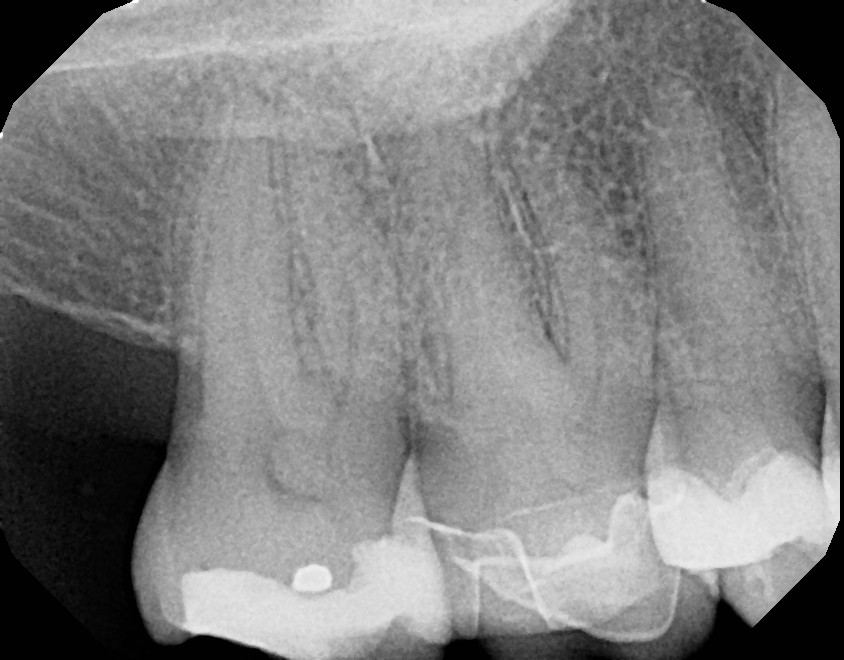

This is a first maxillary molar (tooth #3) that over time required a crown due to a large failing filling. On average, fillings last 5-8 years depending on the size and type of filling with proper oral hygiene, including daily flossing. This patient was advised of possible sensitivity that can occur after crown preparation. Prior to final/permanent crown cementation, tooth #3 became extremely sensitive to hot, cold, and bite and required root canal therapy. With patient education and referral to an endodontist, the final crown was not cemented on prior to root canal therapy. This avoided additional, unnecessary steps. Always ask your dentist/endodontist questions if you feel something doesn't feel right with your teeth, especially after dental work.